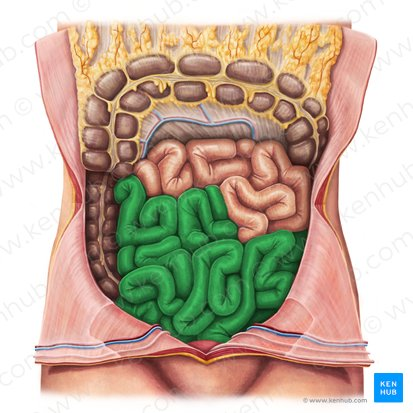

Ileum

The final and longest section of the small intestine, which controls the passage of material into the large intestine.

primarily absorbs vitamin B12, bile salts, and any remaining nutrients, and also plays a role in the transport of water and electrolytes.

Appendix

a small, finger-like pouch attached to the large intestine.

Ascending Colon

The part of the large intestine that travels upward from the cecum along the right side of the abdomen.

Ileocecal Valve

A sphincter muscle situated at the junction of the ileum and the cecum, which controls the flow of chyme from the small intestine into the large intestine and prevents backflow.

Cecum

A pouch-like structure connected to the junction of the small and large intestines.

Appendix

A small, finger-like pouch attached to the cecum.

Ileum

The final and longest section of the small intestine, which absorbs vitamin B12, bile salts, and any remaining nutrients.

Transverse Colon

The part of the large intestine that travels across the abdomen from right to left.

Taenia Coli

Three longitudinal bands of smooth muscle on the outer surface of the large intestine that create haustra.

Descending Colon

The part of the large intestine that travels downward along the left side of the abdomen.

Haustrum